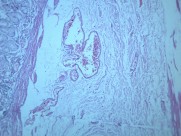

慢性萎缩性胃炎大全(12)张

本病以胃粘膜萎缩变薄,粘膜腺体减少或消失,并伴有肠上皮化生,固有膜内多量淋巴细胞、浆细胞浸润为特点。本性胃炎的病因比较复杂,部分可能与吸烟酗酒和用药不量有关,部分由慢性浅表性胃炎迁移发展而来,还有部分属兔自身免疫疾病。